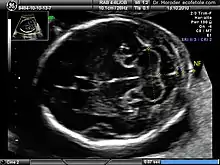

A nuchal scan or nuchal translucency (NT) scan/procedure is a sonographic prenatal screening scan (ultrasound) to detect chromosomal abnormalities in a fetus, though altered extracellular matrix composition and limited lymphatic drainage can also be detected.[1]

There are two distinct measurements: the size of the nuchal translucency and the thickness of the nuchal fold. Nuchal translucency size is typically assessed at the end of the first trimester, between 11 weeks 3 days and 13 weeks 6 days of pregnancy.[3] Nuchal fold thickness is measured towards the end of the second trimester. As nuchal translucency size increases, the chances of a chromosomal abnormality and mortality increase; 65% of the largest translucencies (>6.5mm) are due to chromosomal abnormality, while fatality is 19% at this size.[2] A nuchal scan may also help confirm both the accuracy of the pregnancy dates and the fetal viability.

Procedure

Nuchal scan (NT procedure) is performed between 11 and 14 weeks of gestation, because the accuracy is best in this period. The scan is obtained with the fetus in sagittal section and a neutral position of the fetal head (neither hyperflexed nor extended, either of which can influence the nuchal translucency thickness). The fetal image is enlarged to fill 75% of the screen, and the maximum thickness is measured, from leading edge to leading edge. It is important to distinguish the nuchal lucency from the underlying amniotic membrane.[8]

Normal thickness depends on the crown-rump length (CRL) of the fetus. Among those fetuses whose nuchal translucency exceeds the normal values, there is a relatively high risk of significant abnormality.